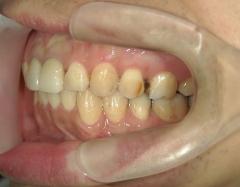

矯正歯科 治療後矯正歯科 全顎ワイヤー矯正 治療後矯正歯科(全顎ワイヤー矯正)治療後

矯正歯科 治療後 E-AMXというセラミックにて左右上1番を被せ直しました。